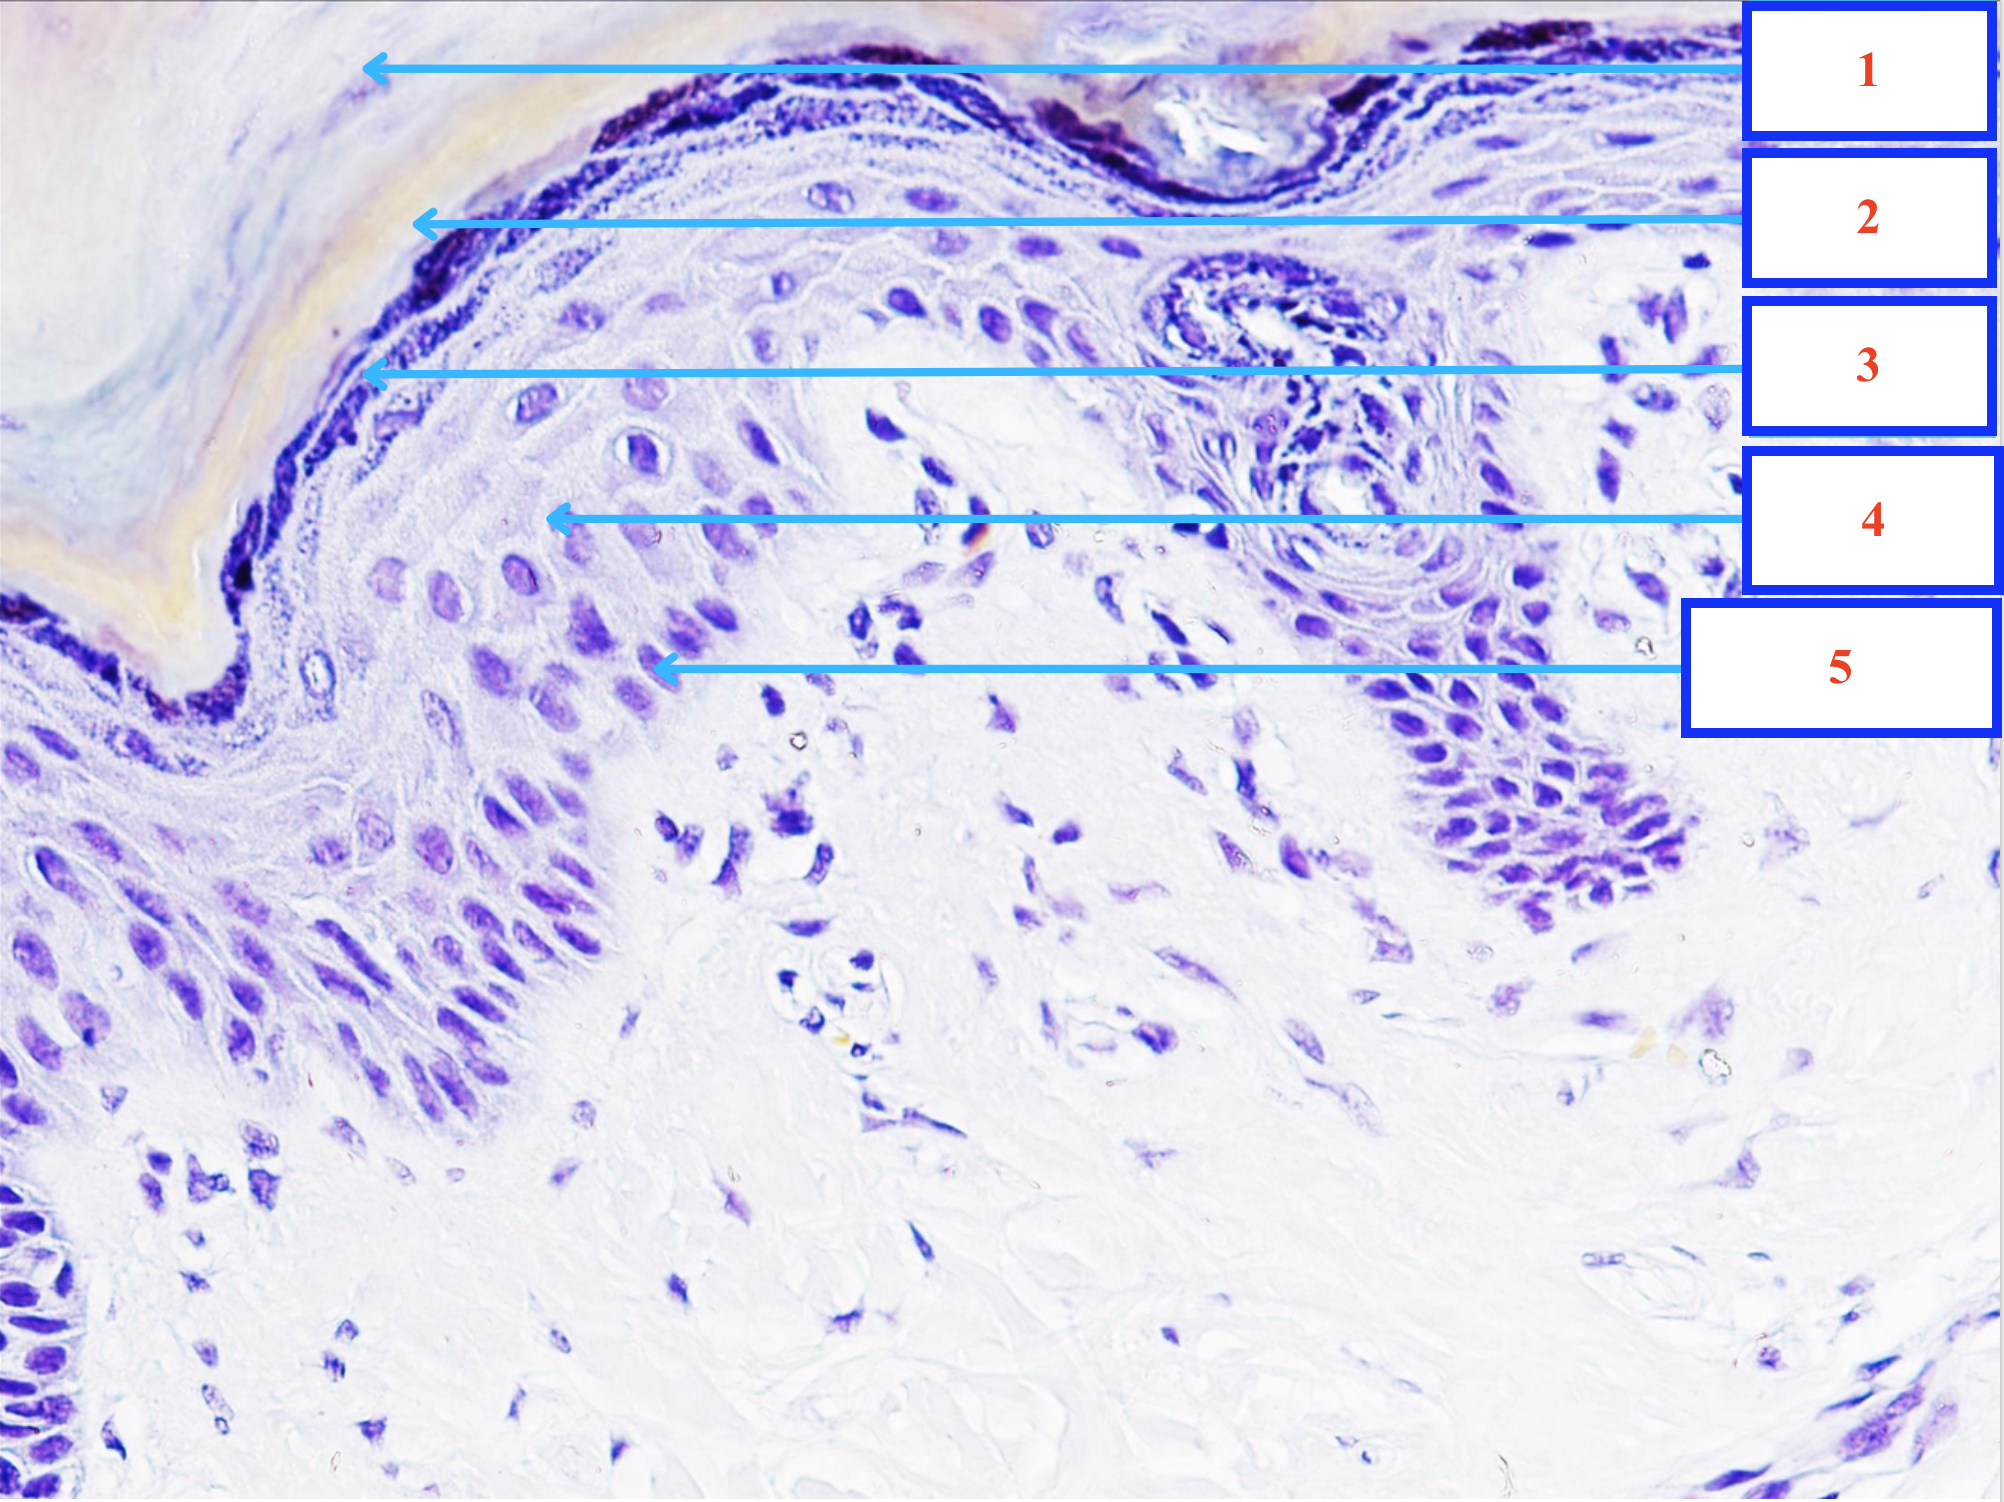

Lớp gì - Tiêu bản gì ?

Lớp sừng của da

Lớp bóng của da

Lớp hạt của da

Lớp gai của da

Lớp sinh sản của da

Tầng gì - Tiêu bản gì ?

Tầng niêm mạc - thực quản

1.2.3. Lớp gì ? - tiêu bản gì ?

Lớp trung gian thực quản

Lớp bề mặt thực quản

Lớp sinh sản thực quản

Nguyên bào sợi